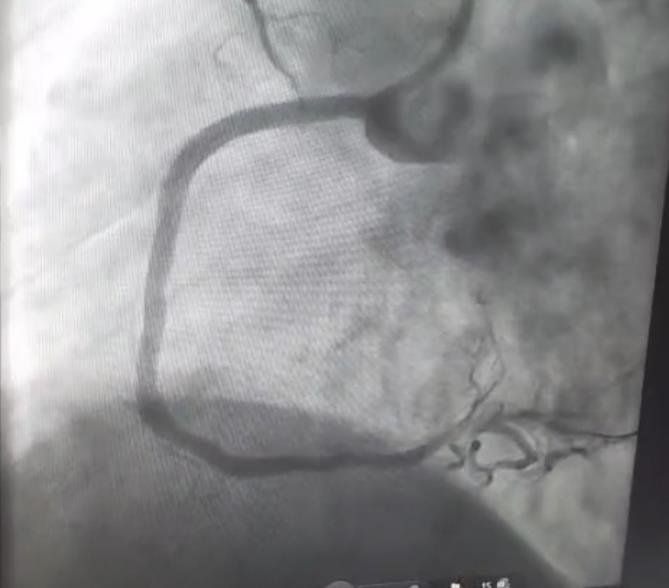

Coronary Angiography Findings (CAG)

Vessel Lesion

• RCA 99% proximal stenosis, 80% mid stenosis (culprit)

• LAD Total chronic occlusion (non-culprit)

• OM1 60% plaque (non-culprit)

Diagnosis: Triple Vessel Disease (TVD)